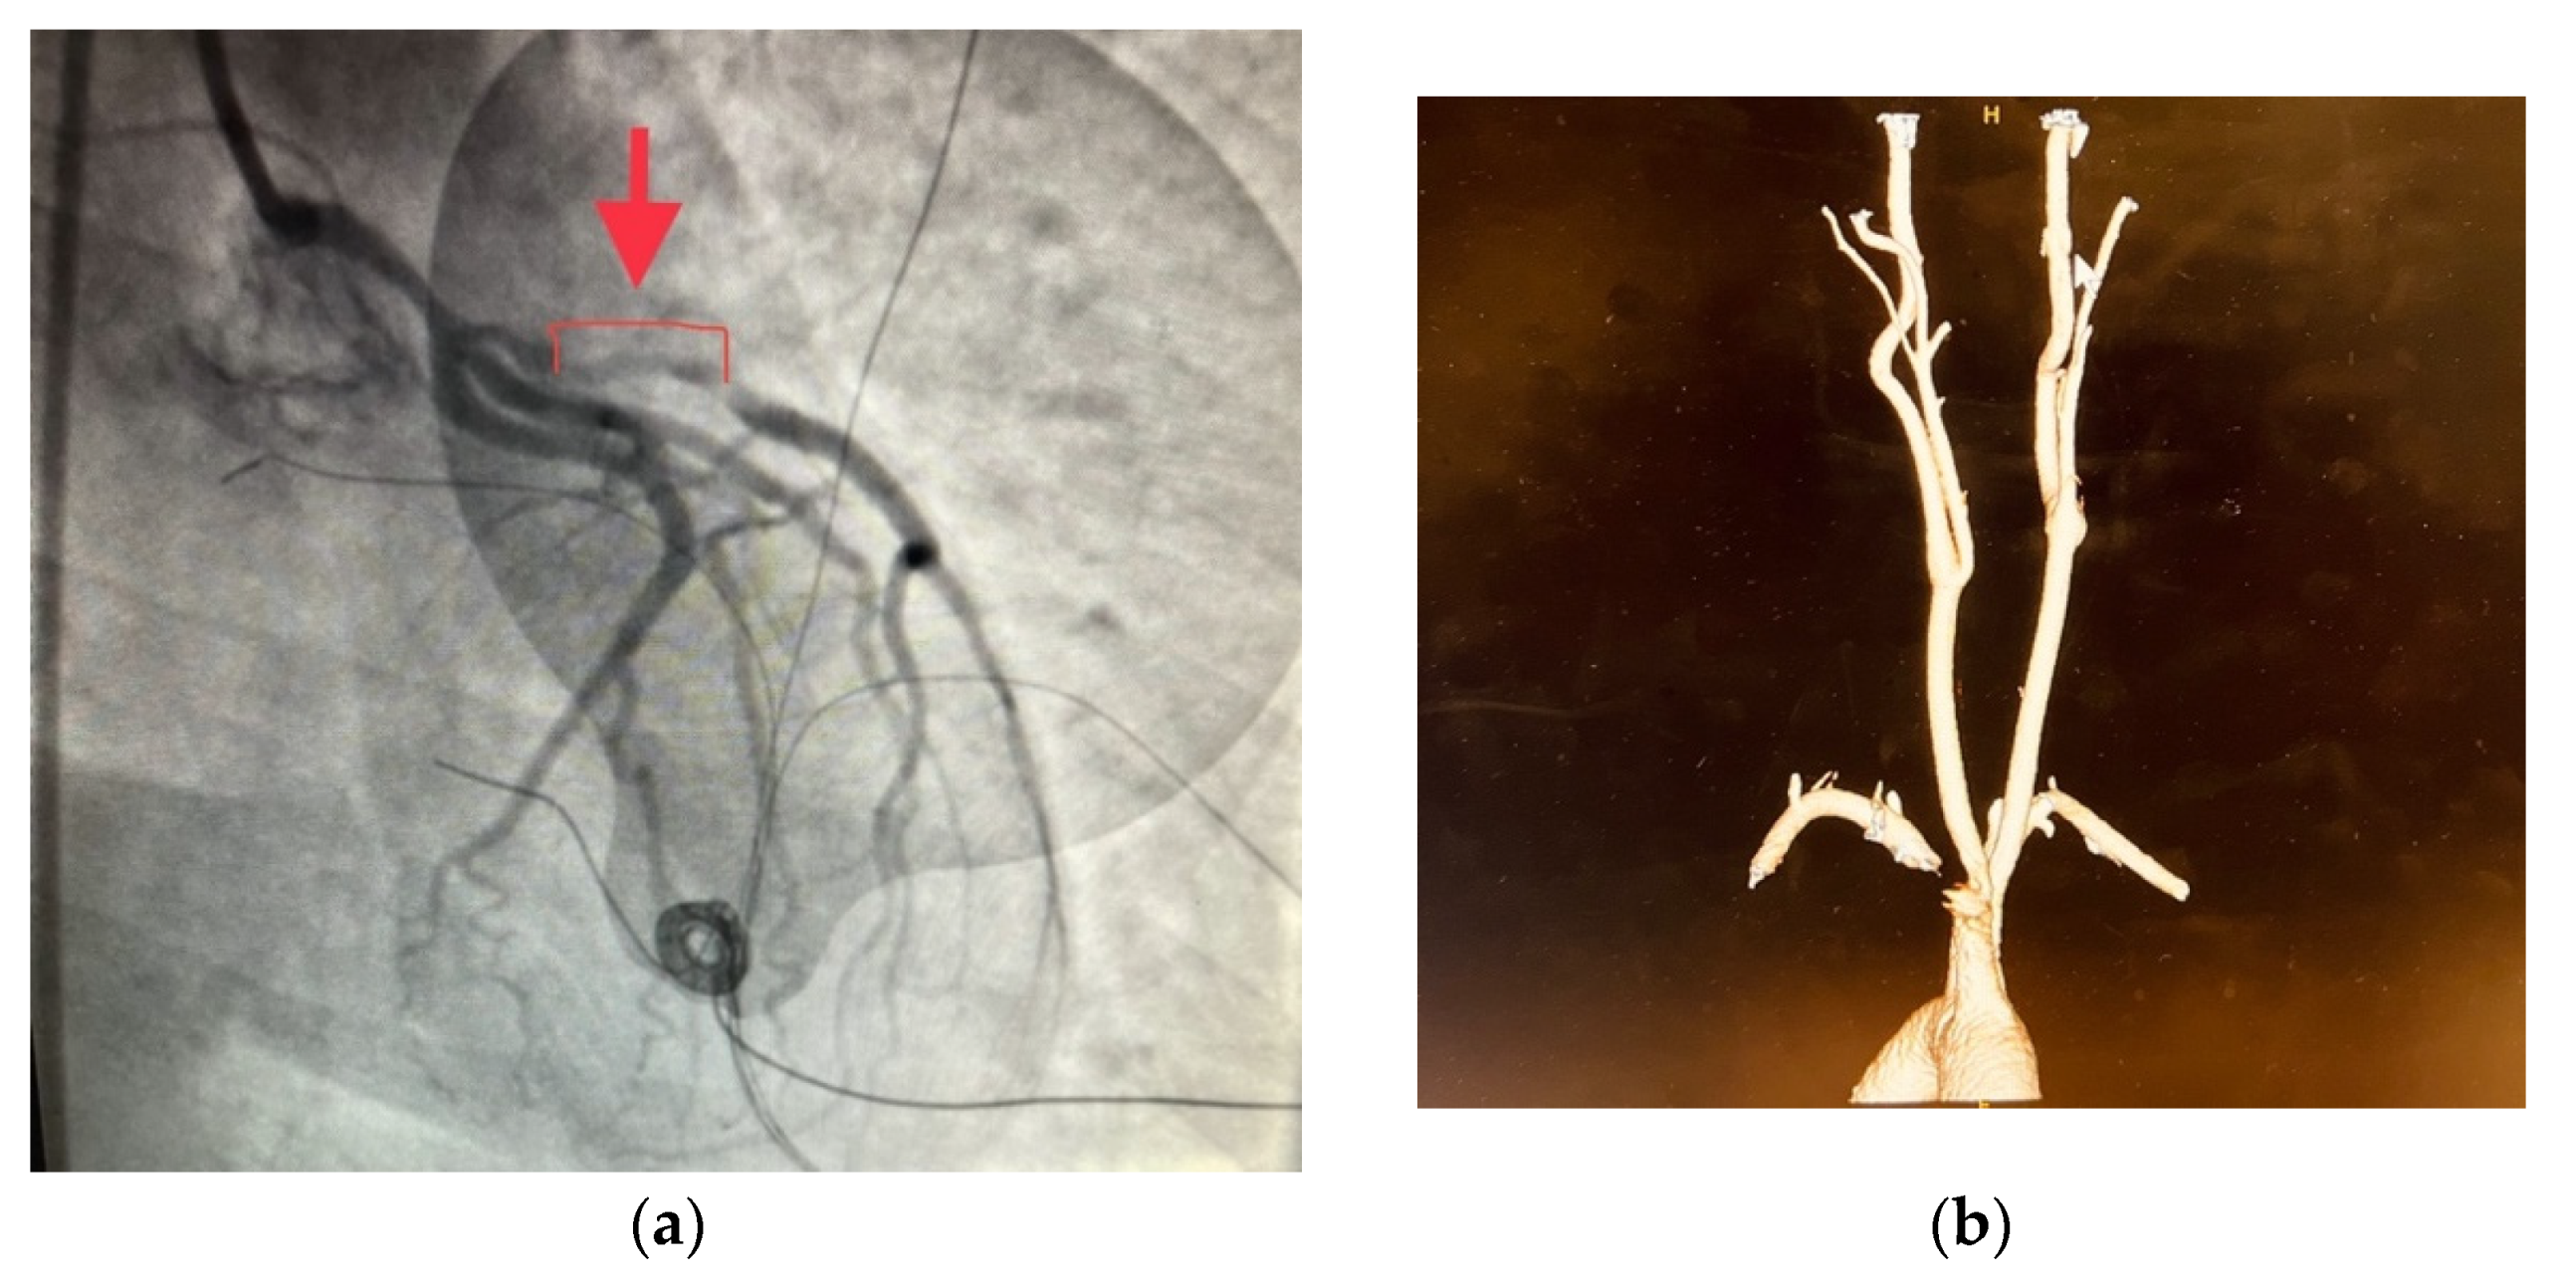

3. Results

4. Discussions